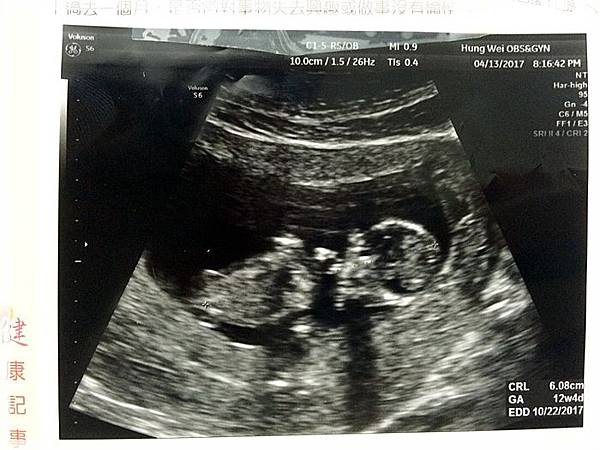

今天是產檢日,這次帶了紜紜妞妞一起去

也是該讓她們姐妹倆知道麻咪肚子裡有小BABY的時候了

產檢時紜姐姐一臉不敢置信的樣子...

她沒想到她又要當姐姐了呀![]()

不過紜紜妞妞都很期待她們弟弟的到來喔![]()

產檢完我們去吃原味燉品屋補一下![]()

這是第一次產檢時的超音波相片...

這是第二次產檢時的超音波相片...

這是第三次產檢也就是這次產檢時的超音波相片...

歡迎你的到來...樂樂![]()